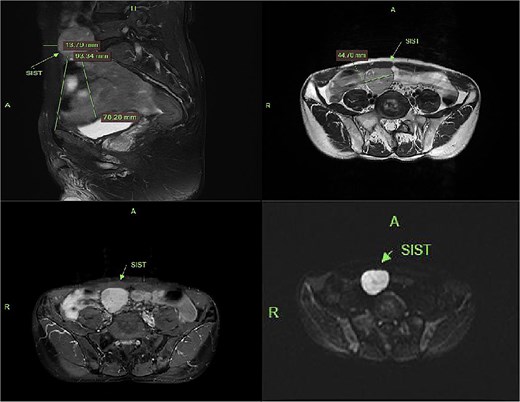

Contrast-enhanced CT demonstrated a well-circumscribed, round enhancing mass measuring 4 cm in diameter. Sagittal imaging showed the lesion positioned 0.9 cm from the bladder wall, 4.5 cm from the anterior abdominal wall, and 6.1 cm from the pubic symphysis (Fig. 2). The mass exhibited an intact capsule without evidence of rupture. MRI performed within a 24-hour period, sagittal imaging showed the lesion positioned 7.9 cm from the bladder wall, 1.3 cm from the anterior abdominal wall, and 9.3 cm from the pubic symphysis, and confirmed stable positioning and morphology, maintaining identical spatial relationships to adjacent structures (Fig. 3).

MRI demonstrates superior displacement of the tumor compared to CT, with isointense signal on T2-weighted fat-suppressed sequences, post-contrast enhancement, and hyperintensity on DWI at a b-value of 800 s/mm².

SISTs typically follow an insidious and asymptomatic course, frequently discovered incidentally during imaging performed for unrelated indications. Preoperative diagnosis relies primarily on imaging, with relatively high diagnostic yield for larger tumors. In this case, the tumor was an incidental finding during a bladder-oriented examination. It did not cause significant bladder compression or associated symptoms, such as urinary frequency. CT provided detailed multiplanar information, revealing a pelvic mass surrounded by abundant bowel loops. Following contrast CT, the tumor exhibited significant and relatively homogeneous enhancement without calcification; these features are typical for GISTs [3]. The absence of bowel preparation, combined with intraluminal gas and indistinct perilesional omental fat, complicates differentiation from entities such as small intestinal lymphoma. MRI demonstrated anterior and superior displacement of the mass relative to its position on CT. On T1-weighted images, the lesion demonstrated low to intermediate signal intensity (SI), while T2-weighted images revealed heterogeneous SI. Fat-saturated sequences showed no evidence of low signal intensity. Diffusion-weighted imaging (DWI) and apparent diffusion coefficient (ADC) mapping confirmed the solid nature and high cellularity of the mass, characteristic features of abdominal mesenchymal tumors. Further evaluation indicated the tumor arose from the muscularis propria of an adjacent bowel loop, with a tendency to displace rather than invade surrounding structures.